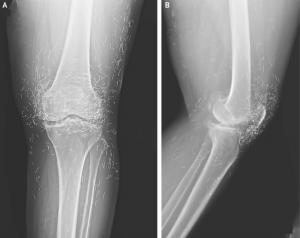

Doctors Stunned After X-Ray Reveals Dozens of Gold Acupuncture Needles in Woman’s Knees

But that’s exactly what happened when her X-ray revealed something unusual: dozens of tiny gold acupuncture needles still embedded in the joint area.

According to a case published in the New England Journal of Medicine, her treatment involved needles that were inserted and intentionally left behind — a practice sometimes used in parts of Asia with the belief that long-term stimulation may help reduce joint pain.

Radiologist Dr. Ali Guermazi, who commented on the case, noted that embedded needles may also prevent patients from safely undergoing MRI scans, as metallic objects can shift or heat during the procedure.